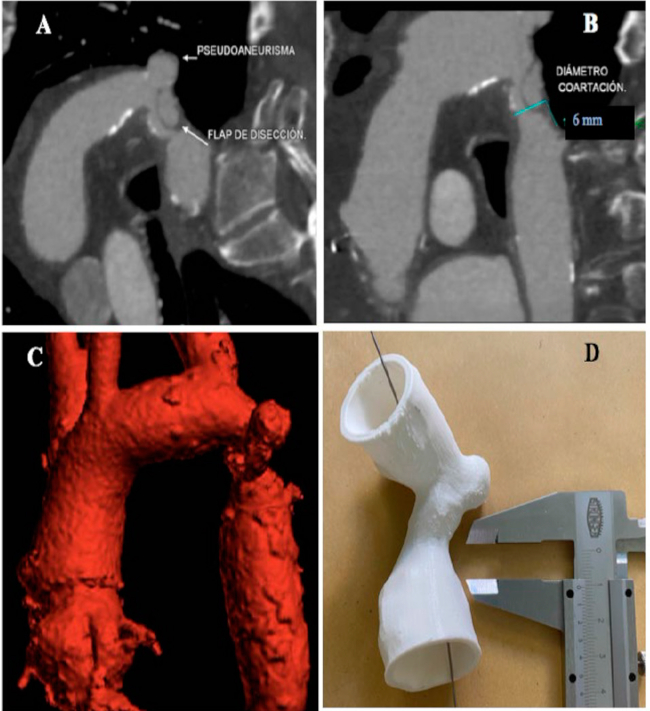

El motivo de su internación fue una claudicación intermitente con progresión en los últimos meses a dolor a los pocos metros. El laboratorio constató una anemia significativa asociada a una insuficiencia renal. En ese momento el paciente refirió haberse accidentado hacía unos meses, con una importante pérdida de sangre por una epistaxis. Luego de optimizar los parámetros de laboratorio con hidratación y transfusiones, se realizó una angiotomografía de tórax, abdomen y pelvis (Figura 1). En ese estudio se reconocieron las huellas quirúrgicas del reemplazo de la aorta ascendente con el tubo valvulado y, en el tercio proximal de aorta descendente, inmediatamente posterior al origen de la arteria subclavia izquierda, se evidenció una recoartación aórtica con una longitud de 22 mm y un diámetro de 6 mm asociado a un pseudoaneurisma anastomótico.

Se decidió hacer un tratamiento endovascular de la recoartación. Para una optimización de la estrategia se realizó la reconstrucción y la impresión 3D de la aorta patológica (Figura 1).